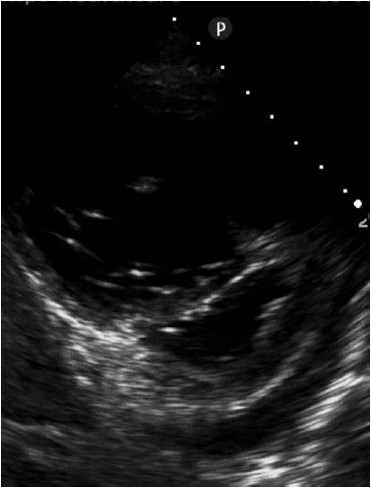

Paciente se apresenta no setor de emergência de hospital com dispneia em repouso. Ao realizar ecocardiografia direcionada, é encontrada a imagem a seguir, a qual sugere

(Arquivo pessoal; imagem usada com autorização)